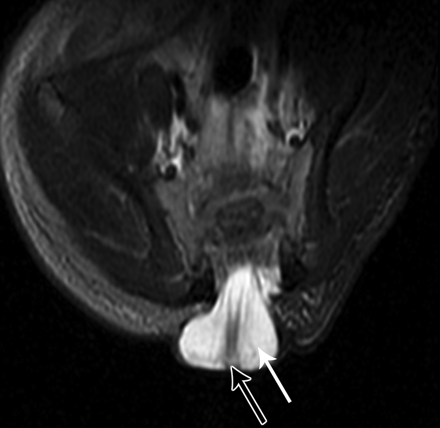

Терминальное миелоцистоцеле

Приложения:

3.cover_.giff20.medium._terminal_myelocystocele..giff21.medium._terminal_myelocystocele..giff22.medium._terminal_myelocystocele..gif

Миелоцистоцеле представляет собой грыжевое выпячивание в дефект позвоночника оболочек и спинного мозга с резко расширенным центральным каналом, так что спинной мозг как бы является стенкой грыжевого мешка.